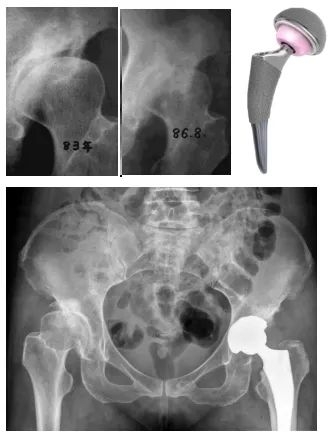

(35岁患者诊断DDH后未及时矫正,3年发展为髋骨关节炎行全髋关节置换术)虽然目前的人工全髋关节置换手术已经非常成熟,效果满意,但是仍然存在人工关节假体使用寿命年限的问题,而且也存在感染和脱位等并发症。尤其是年轻人,还不得不面对人工关节使用年限到了之后再次翻修的问题。因此如何避免早期DDH患者发展为髋骨关节炎,成为了关节外科医生不得不面对的事情。

髋臼周围截骨术模拟图